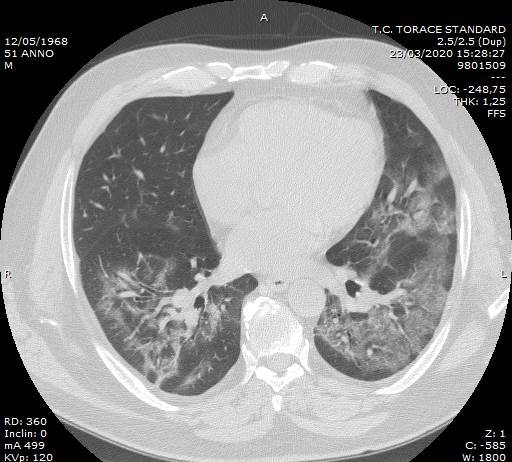

Maschio, 51 anni. Anamnesi patologica remota muta. Il paziente è residente a Fabrizia,...

Maschio, 51 anni. Anamnesi patologica...